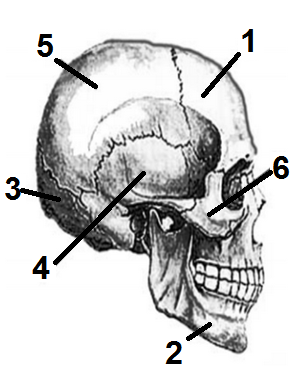

Анатомические изображения срединной сагиттальной линии черепа